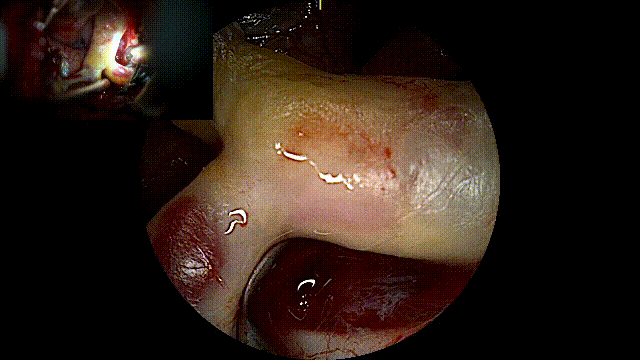

左侧改良翼点入路,打开侧裂

暴露动脉瘤近端M1段载瘤动脉

分离破裂出血动脉瘤

临时阻断M1段,充分分离动脉瘤瘤颈并夹闭

使用AR增强现实荧光,可在自然解剖结构下看到动脉瘤无荧光信号通过,瘤颈被完全夹闭